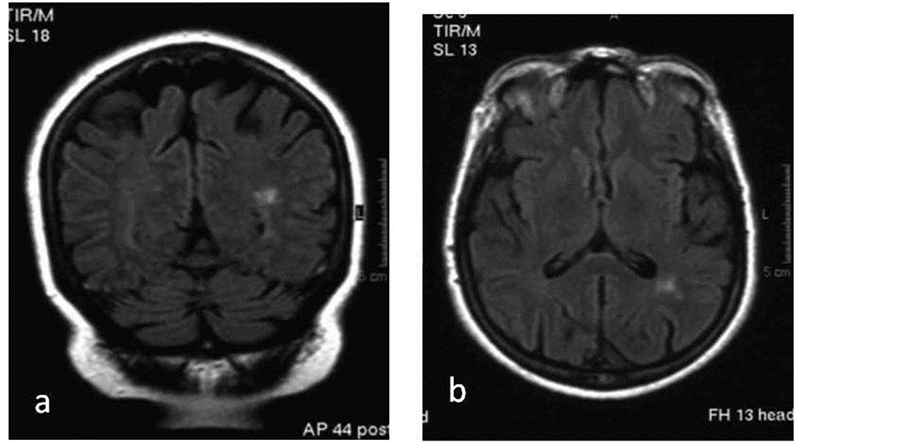

The second patient with seizures revealed small focal lesions less than 1 mm bilateral in the periventricular and subcortical white matter with intense enhancement on the left parietal and right frontal lobe (Figure 2).

Figure 2. (a) Coronal, (b) axial FLAIR sequences show small lesions adjacent to the left occipital horn.